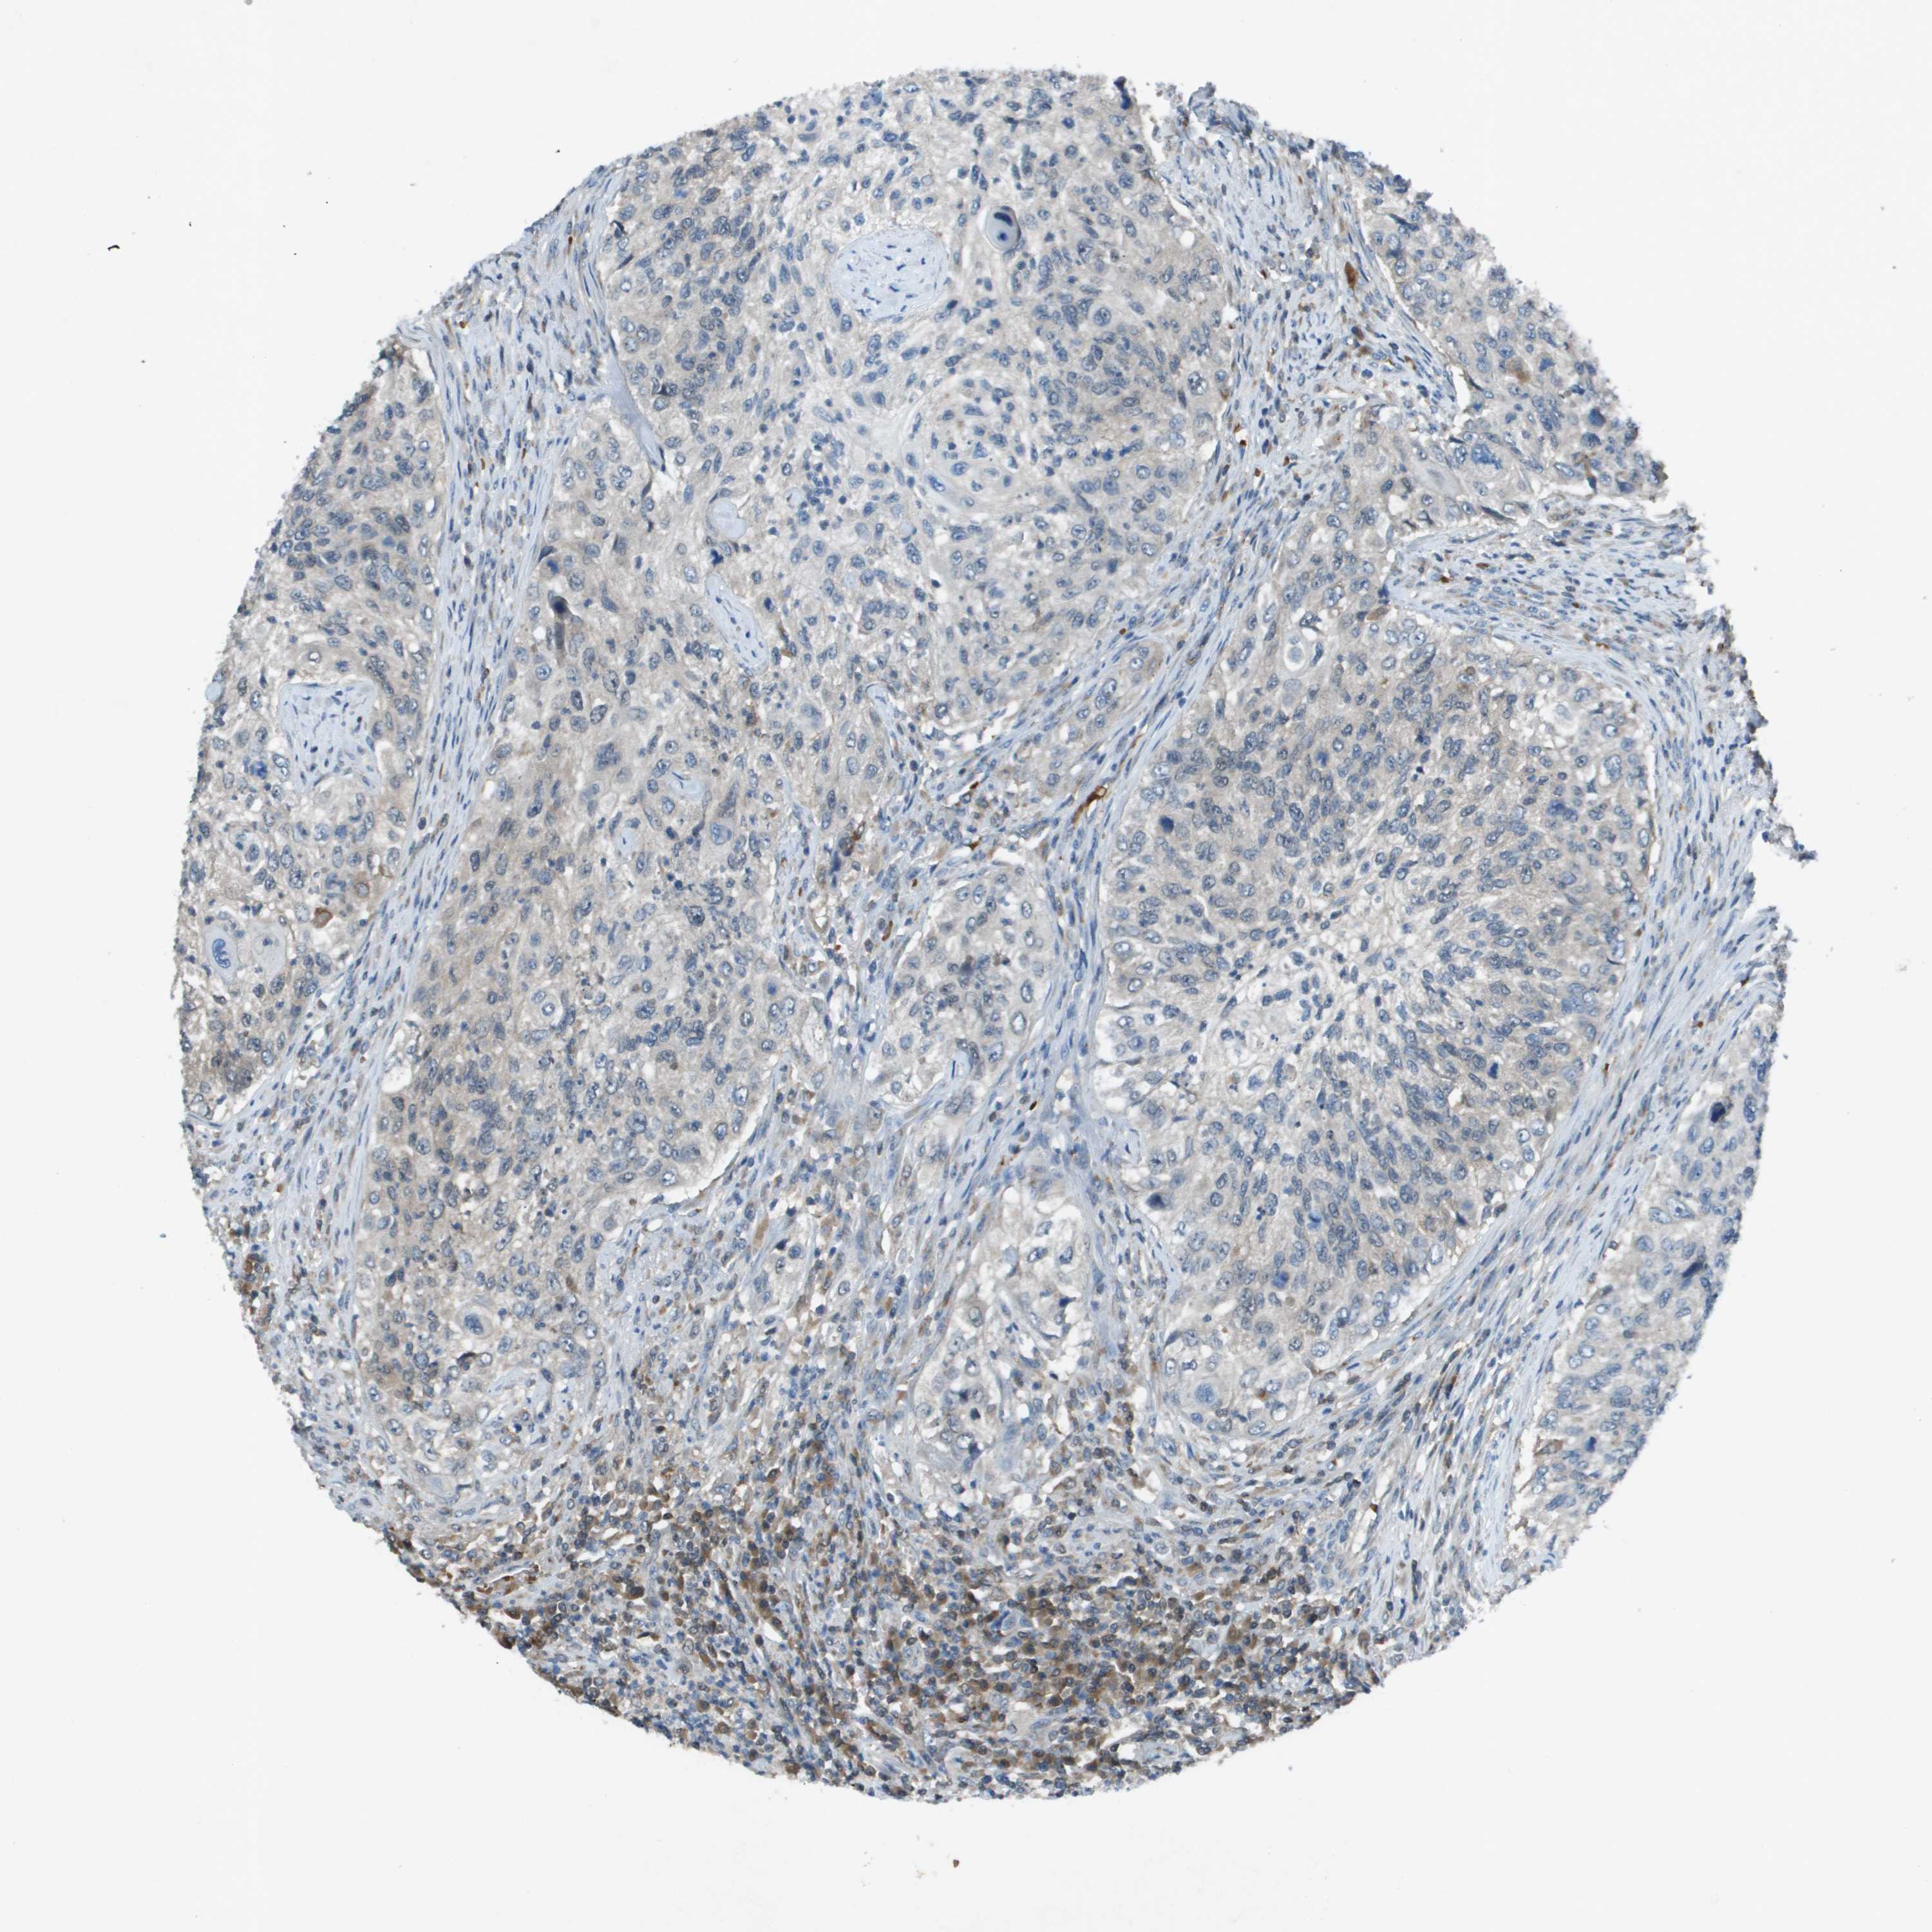

UROTHELIAL CANCER - Protein expressioni

A mouse-over function shows sample information and annotation data. Click on an image to view it in a full screen mode. Samples can be filtered based on level of antibody staining by selecting one or several of the following categories: high, medium, low and not detected. The assay and annotation is described here.

Antibody stainingi

Antibody staining in the annotated cell types in the current human tissue is reported as not detected, low, medium, or high, based on conventional immunohistochemistry profiling in selected tissues. This score is based on the combination of the staining intensity and fraction of stained cells.

Each image is clickable and will lead to virtual microscopy that enables deeper exploration of all samples and also displays staining intensity scores, fraction scores and subcellular localization as well as patient and tissue information for each sample.

Antibody CAB004347

Urothelial carcinoma, Low grade

Urothelial carcinoma, High grade